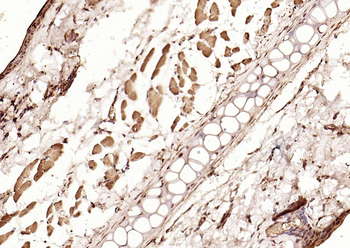

100 μl, 200 μl, 50 μlSMAD7 Rabbit Polyclonal Antibody [orb500819]

FC, ICC, IF, IHC-Fr, IHC-P, WB

Bovine, Porcine

Human, Mouse, Rat

Rabbit

Polyclonal

Unconjugated

100 μl, 200 μl, 50 μlPhospho-Smad3 (Ser213) Rabbit Polyclonal Antibody [orb106193]